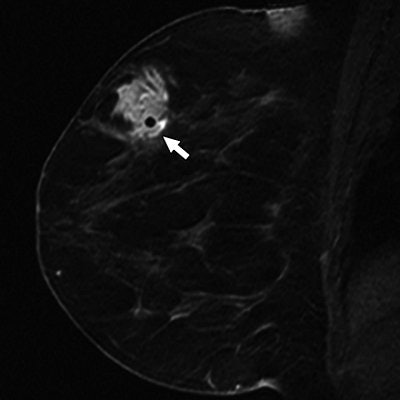

| Same patient as above. Histologic analysis of vacuum-assisted breast biopsy specimen shows ductal carcinoma in situ (DCIS) with solid architecture, intermediate nuclear grade, and central mucin (H and E, x40). Lee J, Kaplan JB, Murray MP, Mazur-Grbec M, Tadic T, Damir Stimac D, and Lieberman L, "Underestimation of DCIS at MRI-Guided Vacuum-Assisted Breast Biopsy" (AJR 2007; 189:468-474). |